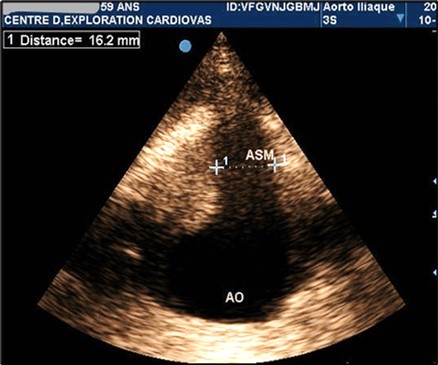

AAAs were fusiform in 23 patients (71.9%). The saccular aneurysm was present in 9 patients (28.1%). Figure 1 and (Figure 2).

Figure 1.Partially thrombosed 5.2cm fusiform suprarenal AAA with extension to the superior mesenteric artery in a 59-year-old subject (CEC 'Saint-Esprit' of the AMP-MCV).

Figure 2.Partially thrombosed 5.2cm fusiform suprarenal AAA with extension to the superior mesenteric artery in a 59-year-old subject (CEC 'Saint-Esprit' of the AMP-MCV).